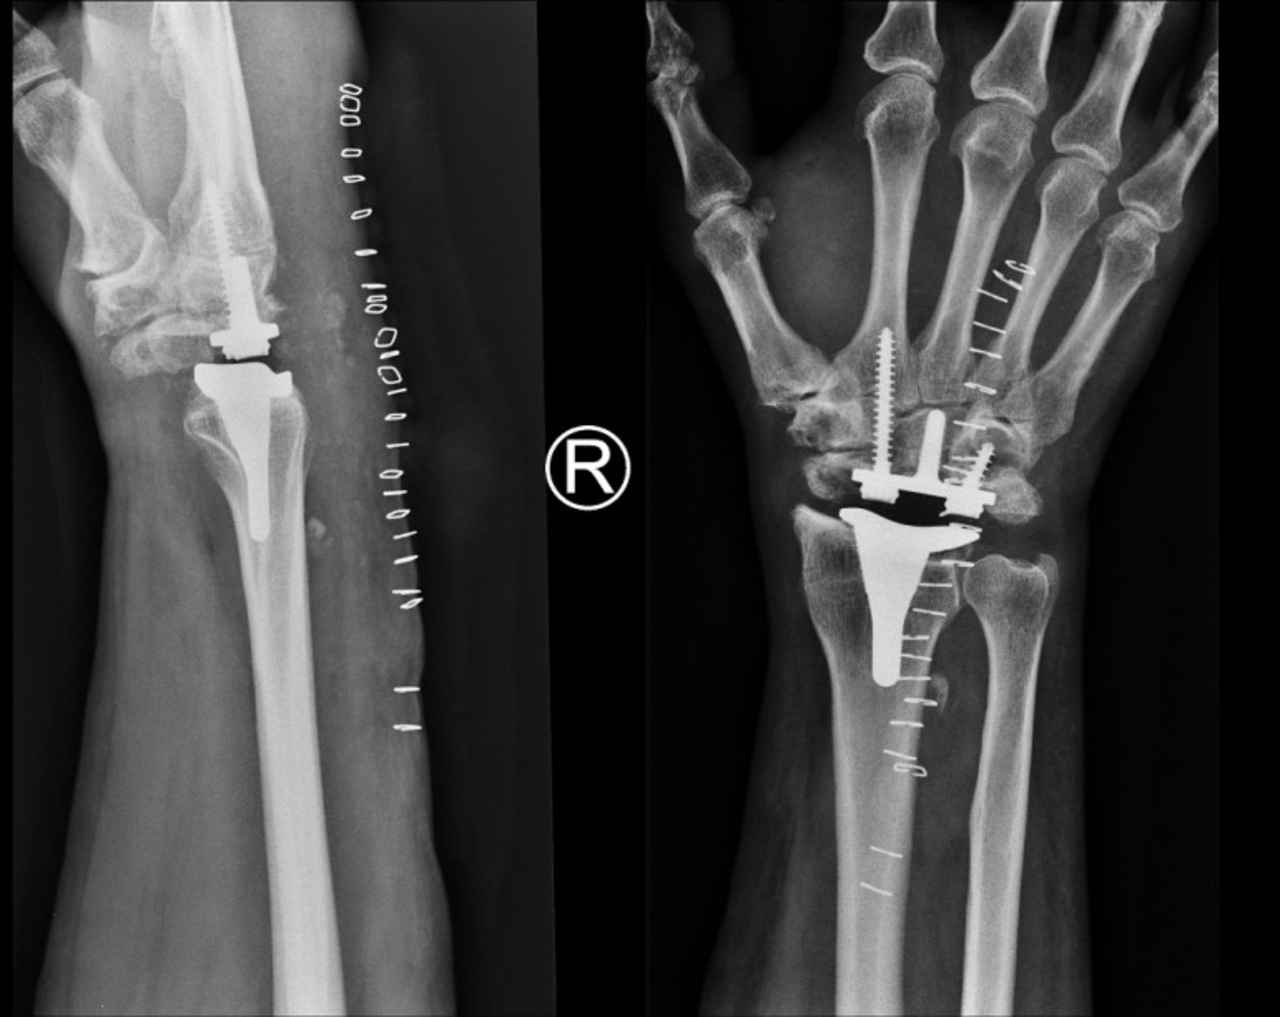

Ortopedzi z Buska-Zdroju przeprowadzili innowacyjny zabieg. Pierwszy taki w Polsce

Specjaliści z powiatowego szpitala w Busku-Zdroju przeprowadzili trudny i rzadko wykonywany zabieg operacyjny założenia endoprotezy nadgarstka.

U operowanego pacjenta w młodości doszło do urazu nadgarstka, co doprowadziło do zwyrodnienia, objawiającego się blokadą ruchu oraz ogromnym bólem.

– Do wymiany stawu nadgarstka dochodzi wtedy, gdy leczenie farmakologiczne nie przynosi pozytywnych efektów. Skutkiem przeprowadzonego zabiegu jest uwolnienie pacjenta od przejmującego bólu, widocznej gołym okiem opuchlizny, oraz usunięcie dolegliwości związanych ze sztywnością stawu. Przed zabiegiem chory nie mógł wykonywać nawet prostych, podstawowych czynności typu: zapinanie odzieży na guziki, posługiwanie się kluczami itp. Po zabiegu  poprawie uległ komfort jego życia, a dolegliwości bólowe ustąpiły – informuje dyrektor lecznicy Grzegorz Lasak.

– Warto podkreślić, że jest to pierwszy w Polsce zabieg z wykorzystaniem konkretnej endoprotezy nadgarstka, renomowanej amerykańskiej firmy. Podobne operacje wykonywane są w naszym kraju wyłącznie na terenie specjalistycznych klinik – dodaje dyrektor.

Zabieg przy asyście lekarza Jacka Piątka przeprowadził doktor Włodzimierz Witwicki. Operacja trwała około dwóch godzin. Pacjent po trzech dniach został wypisany do domu.